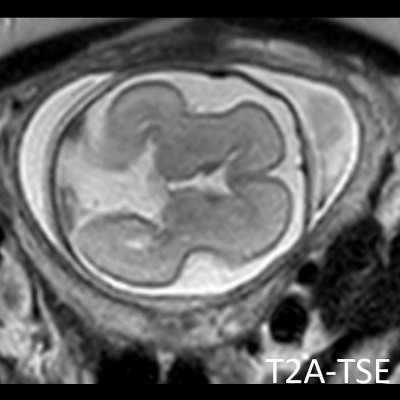

- B) Aksiyel ve sagittal T2A görüntülerde gyrus ve sulkuslarda azalma mevcut olup korteks kalınlaşmış görünümde ve operkulizasyon ayırt edilememiştir. Korteks beyaz cevher ayrımı zor seçilmektedir (ok) Ekstraaksiyel BOS mesafesi artmış görünümdedir (ok). Yapılan ölçümlerde; tegmentovermian açı :8 derece (ok) serebellar vermis boyutları kraniokaudal: 16 mm, aksiyel: 5,5×8,5 mm (ok) ölçülmüş olup BPD:27w ile uyumlu olan fetüste haftasıyla uygun olarak değerlendirilmiştir.